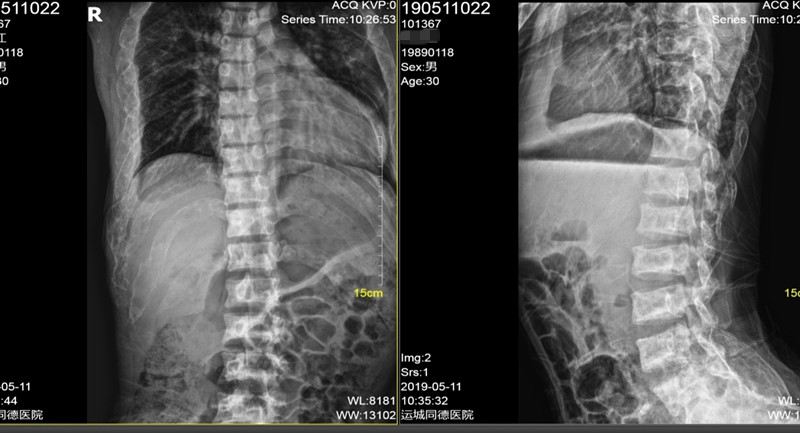

辅助检查:糖化血红蛋白6.2%;甲状旁腺激素87pg/ml(15-65);25-羟维生素D23.63ng/ml(>20) ;血镁0.71mmol/L(0.66-1.07);血钙2.32mmol/L(2.15-2.55) ;血磷0.83mmol/L(0.81-1.45);24小时尿钙3.01nmol/24h(2.5-7.5);24小时尿磷10.9nmol/24h(13-42);TP1NP:1052ng/ml(9.06-72.64);β-CTX :2.68ng/ml(0.043-0.783);骨钙素:255.3ng/ml(24-70);血碱性磷酸酶:691U/L(40-129);血清抗酒石酸酸性磷酸酶:10.3U/L(≤4.47);骨源性碱性磷酸酶:75U/L;人护骨素:110ng/L ;骨密度(DXA):左前臂骨密,Z值-6.9;腰椎骨密度正常;胸腰段正侧位片示:考虑骨纤维异常增殖症伴骨质疏松;颌骨CT示:上颌骨地图样改变,下颌骨囊状空泡、丝瓜瓢状改变,考虑骨纤维异常增殖症;右上肢平片示:囊状膨胀性、丝瓜瓢状改变;胸片:考虑骨纤维异常增殖症。

▼ 胸腰椎正侧位片: